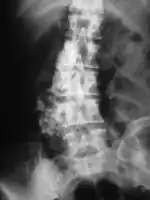

Imaging

Chondrosarcoma spine